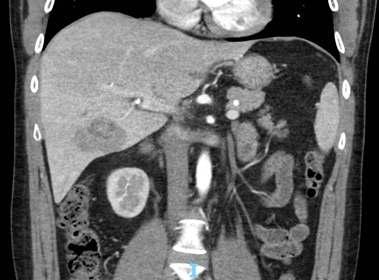

Cierraneste númerounarevisiónsistemáticasobre estatinas y lipoproteína(a), que replantea certezas sobre riesgo cardiovascular, y en nuestro caso clínico del mes un reporte sobre absceso hepático invasivo producido por Klebsiella pneumoniae, recordatorio de la importancia de reconocerentidadesemergentes.

Pág 56. Síndrome de Absceso Hepático Inasivo por Klebsiella Pneumoniae: Presentación de un Caso >>